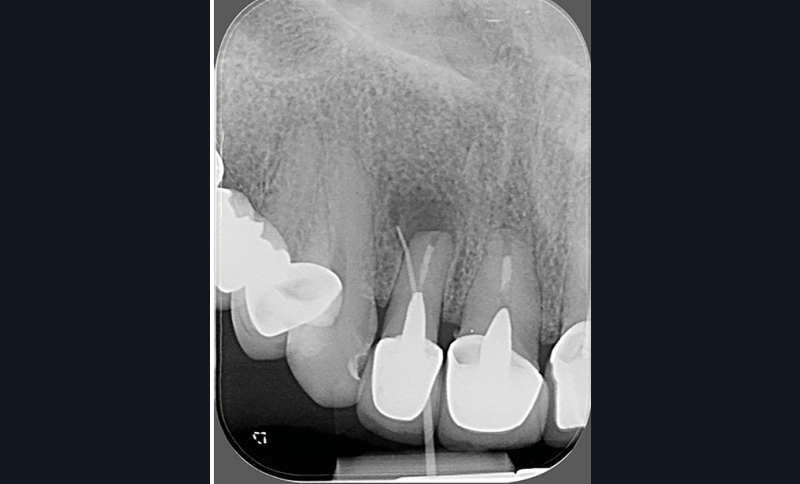

- un retraitement orthograde présente un mauvais rapport bénéfice-risque : par exemple, la présence d’un tenon dont la dépose pourrait fracturer la dent (fig. 2a-b) ;